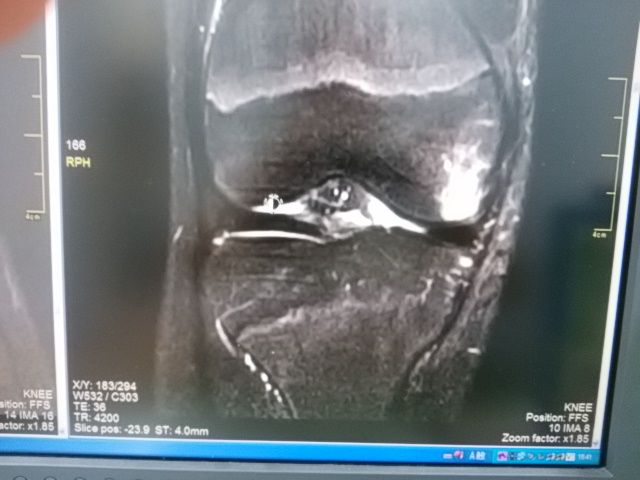

ジャンプの着地で膝を 受傷した プロライダー

歩行困難あるも 単なる打撲かと思いきや 骨挫傷あり

レース出場希望強かったが 軟骨損傷が 怖いため説得   ドクターストップです

しかし 出場していまい

結果オーライ  他に怪我なく 入賞の連絡いただきました    ふー